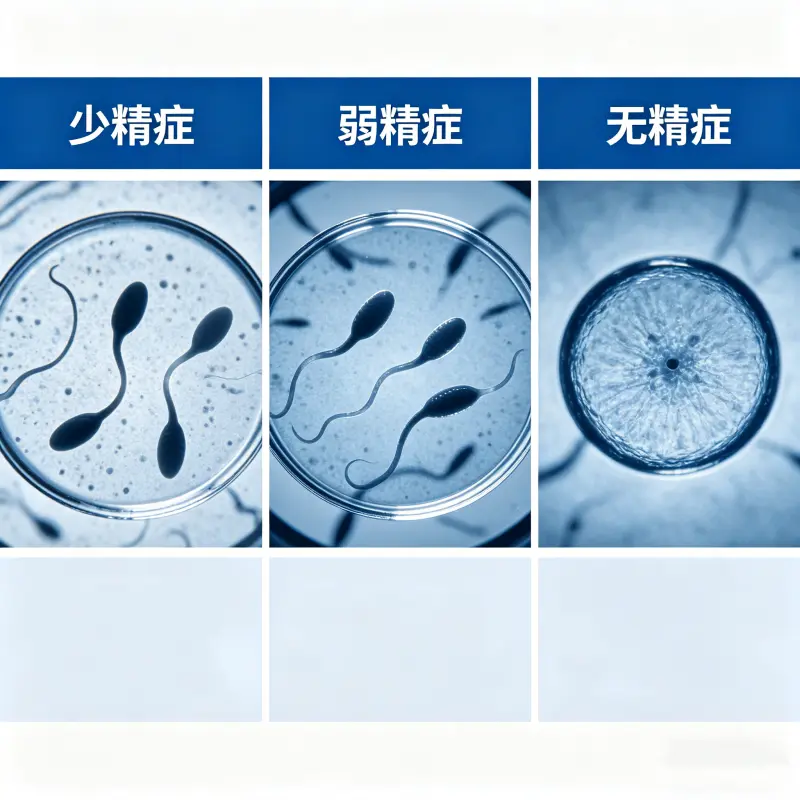

一、什麼是少精、弱精、無精?

在探討「少精、弱精、無精原因」之前,需先了解基本定義:

少精癥(Oligospermia):精子濃度低於1500萬/ml

弱精癥(Asthenozoospermia):精子活動力低於40%

無精癥(Azoospermia):精液中完全沒有精子

這三種情況是影響男性生育能力的主要因素。

少精、弱精、無精